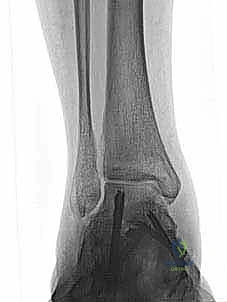

2. التصوير الإشعاعي (الركيزة الأساسية للتشخيص)

لا يمكن الاعتماد على الفحص السريري وحده، خاصة في الحالات المزمنة. يطلب الدكتور هطيف مجموعة من الصور الإشعاعية:

* الأشعة السينية أثناء الوقوف (Weight-bearing X-rays): ضرورية جداً لتقييم محاذاة العظام تحت تأثير وزن الجسم. يتم البحث عن اتساع في المسافة الصافية الإنسية (Medial Clear Space widening)، مما يدل على تمزق رباط الدالية العميق.

* الأشعة السينية مع الإجهاد (Stress Radiographs): يتم التقاط الصور أثناء تطبيق قوة معينة على الكاحل لإظهار عدم الاستقرار الخفي الذي لا يظهر في الصور العادية.